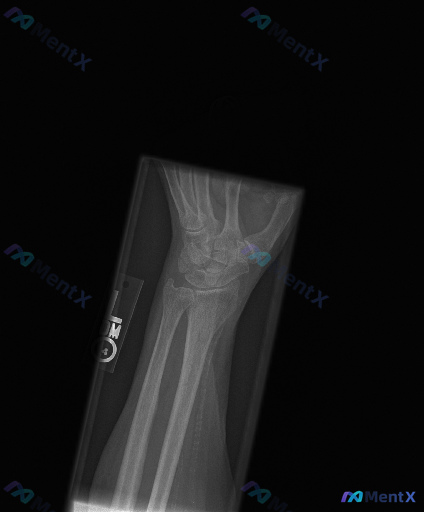

整理到一份影像资料:左侧腕关节斜位X光片,影像科的读片结果如下: 1. 骨骼连续性:舟骨、月骨、三角骨及远排腕骨皮质边缘未见明确中断或骨折线影,舟骨腰部及近极区域骨皮质轮廓相对连续; 2. 关节间隙:腕骨间关节、桡腕关节间隙清晰,宽度无明显增宽或狭窄,未见明显韧带分离征象; 3. 对位排列:腕骨排列...